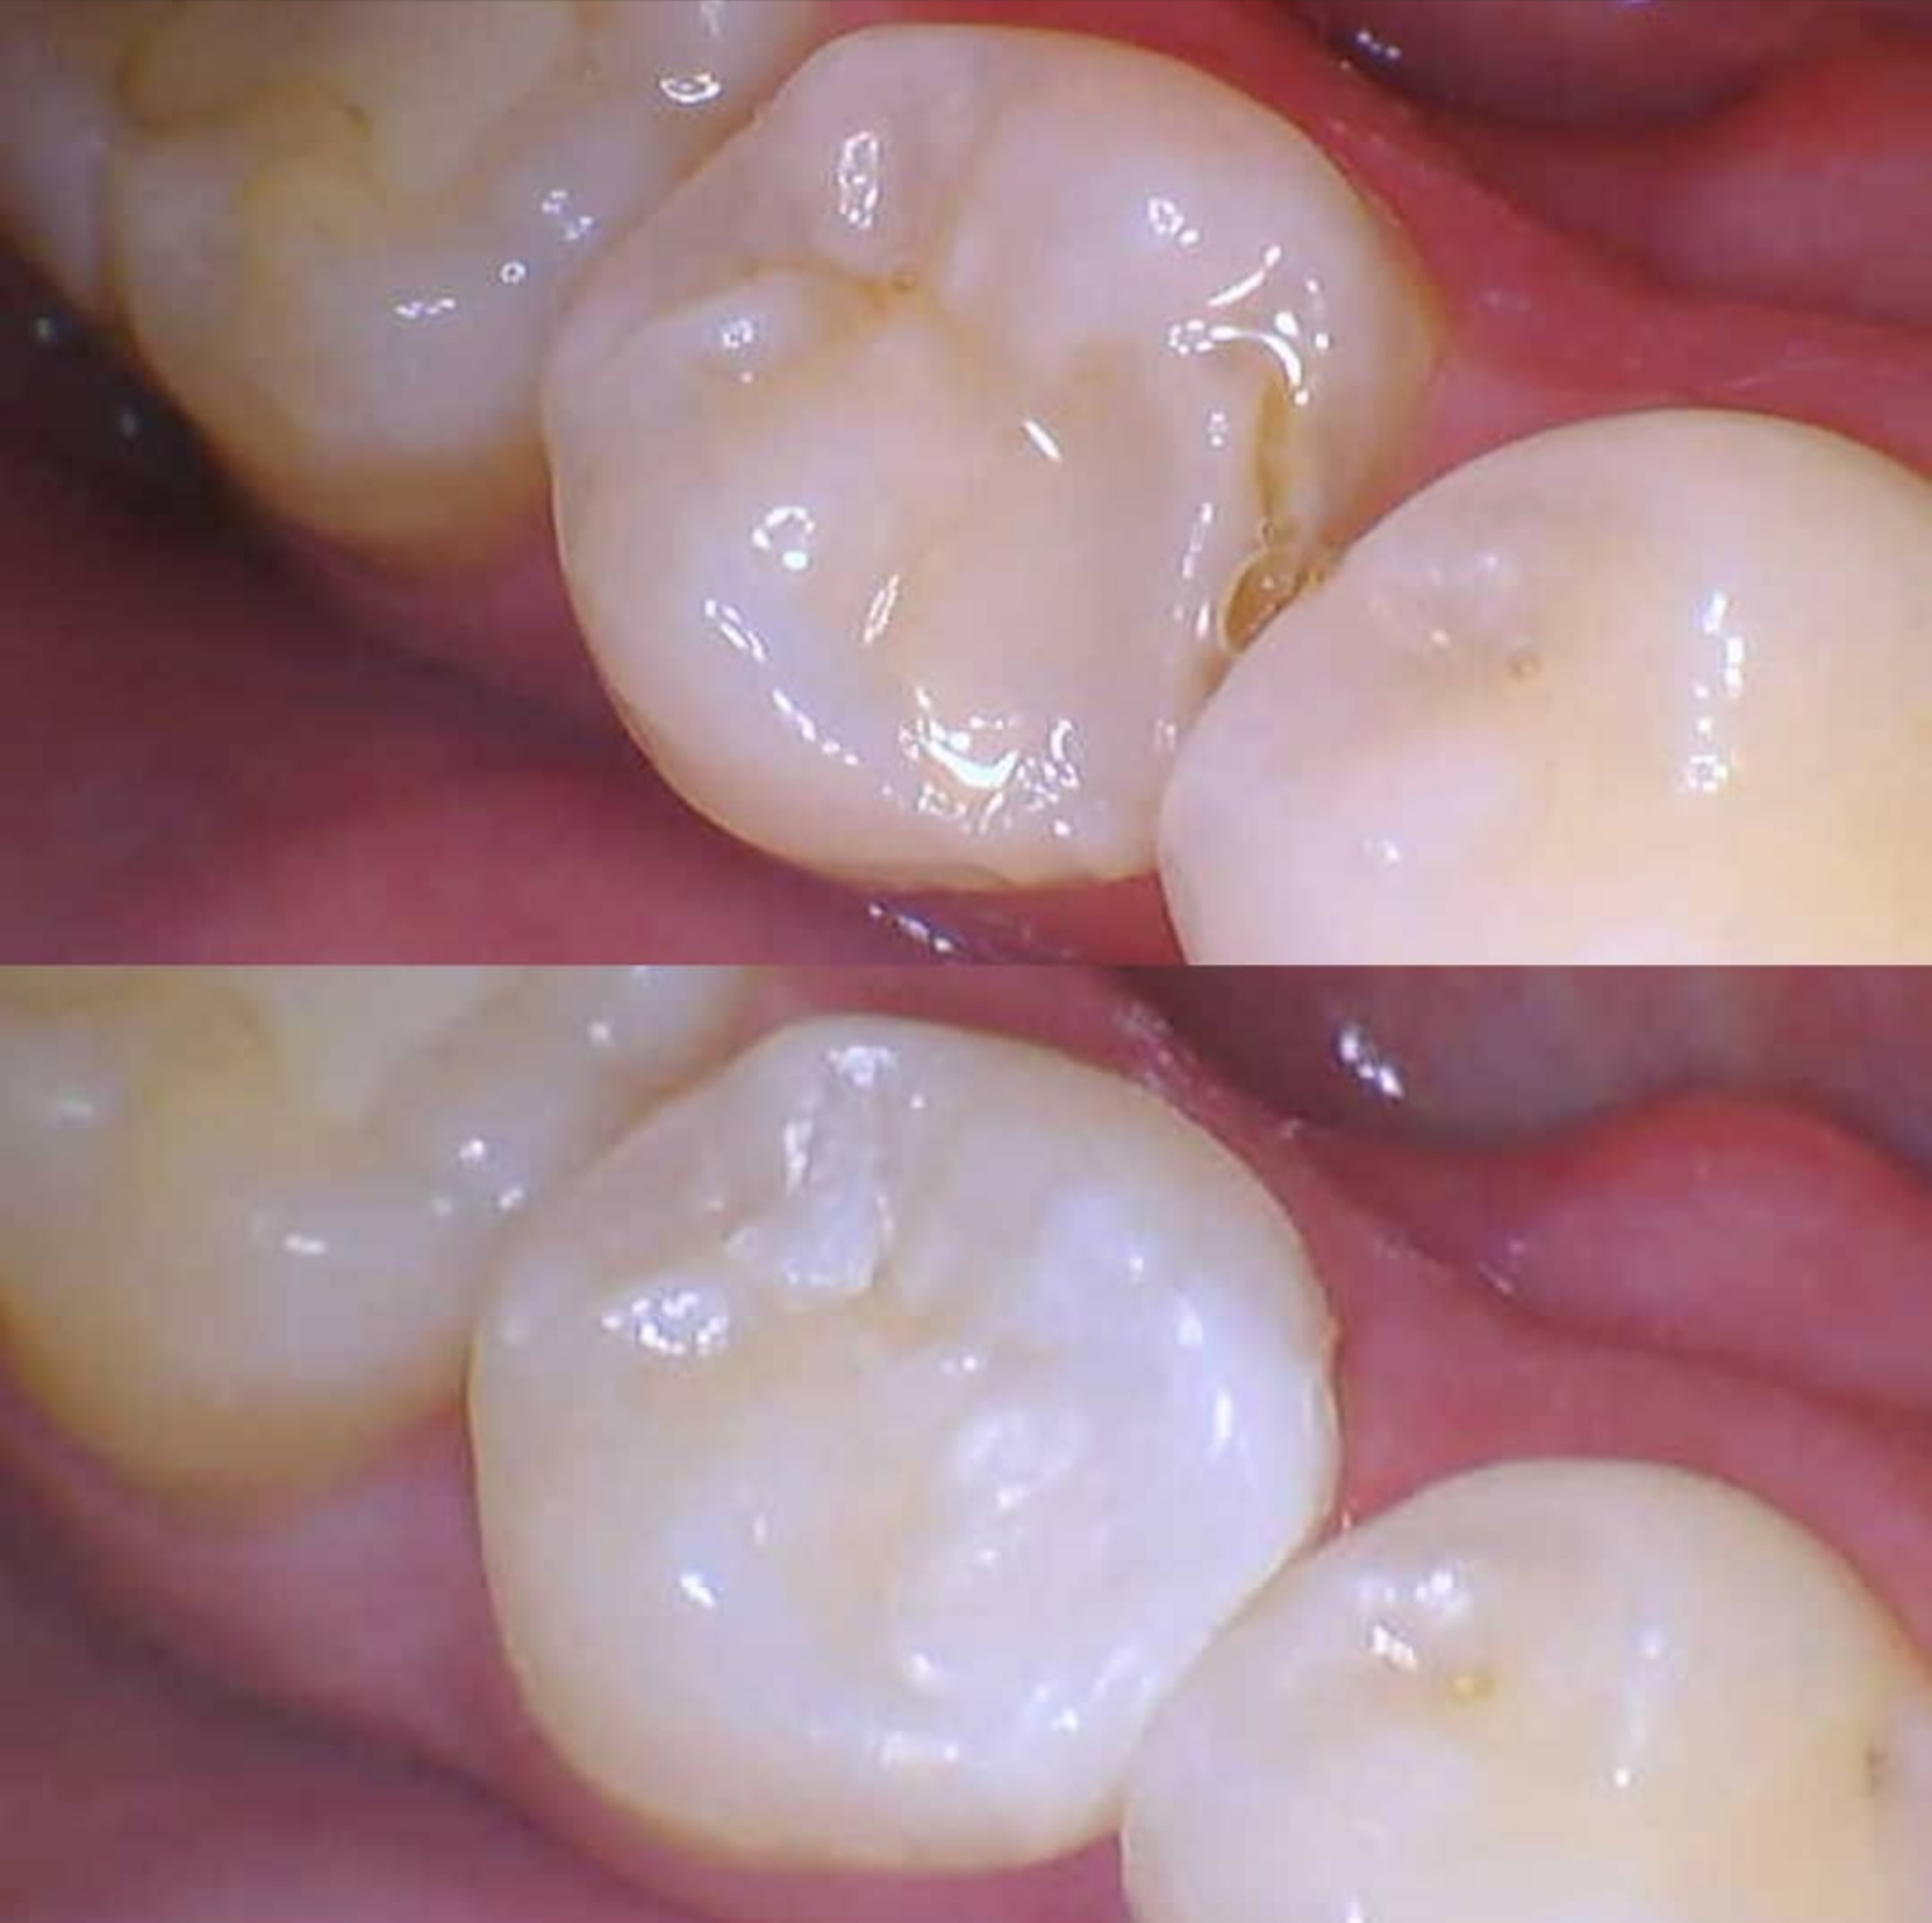

Dr. Whitman Assists Patient With Damaged Filling Causing Gum Discomfort